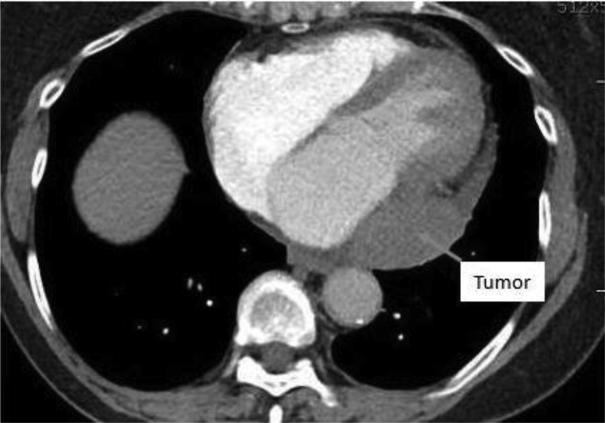

Epicardial Cavernous Hemangioma: A Diagnostic Challenge.

• Primary cardiac tumors, although rare, represent a wide differential diagnosis. • It is often difficult to decipher the type of tumor from imaging alone. • This case highlights imaging modalities to plan surgical removal of cardiac masses.

• 本病例重点介绍了用于规划心脏肿块手术切除的影像学检查方法。